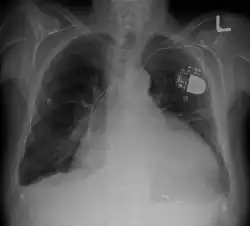

- Pacemaker: Coordinates contractions between ventricles. In people at risk of arrhythmias, drug therapy or an implantable cardioverter-defibrillator (ICD).

- ICDs: Small devices implanted in the chest to monitor heart rhythm and deliver electrical shocks to control abnormal heartbeats. The devices can also work as pacemakers.